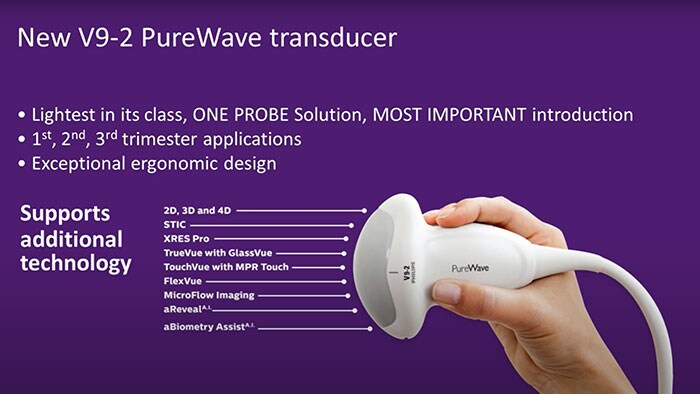

Applications of PureWave Technology to Prenatal Diagnosis

Dr. Luis Goncalves from Phoenix Children’s Hospital shares applications of PureWave technology to prenatal diagnosis.

Dr. Michael Ruma uses the V9-2 PureWave transducer to assist in the diagnosis of a severe fetal intracranial abnormality.